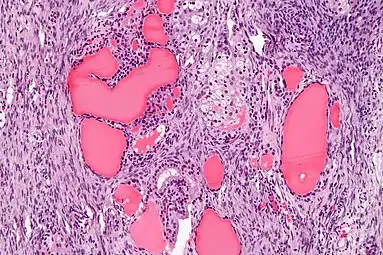

| Micrograph of a struma ovarii. Characteristic thyroid follicles are seen on the right, and ovarian stroma on the left. H&E stain. | |

a-c)Immunohistochemical (CK19, galetin-3, HBME-1) staining of malignant struma ovarii tissues

High magnification Struma ovarii